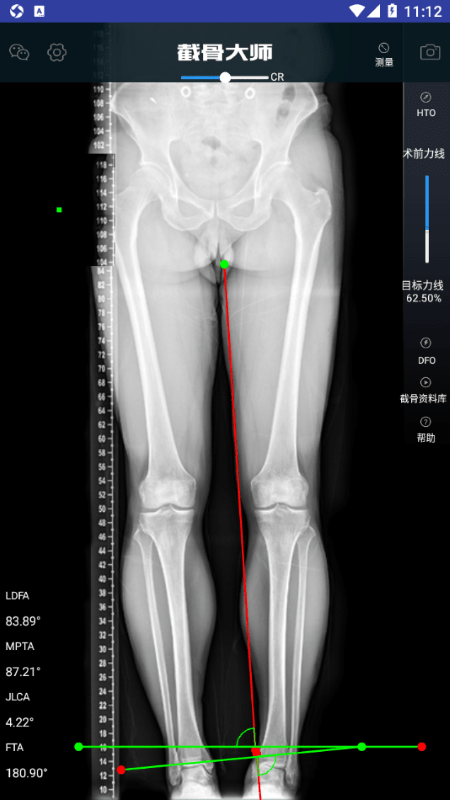

用于胫骨高位截骨术(HTO)和股骨远端截骨术(DFO)的手术效果演示。

测量角度,可以测MPTA、LDFA、FTA、JLCA;

HTO手术效果模拟;DFO手术效果模拟;

设置截骨方式,可以设置开放\闭合,内\外侧等方式;